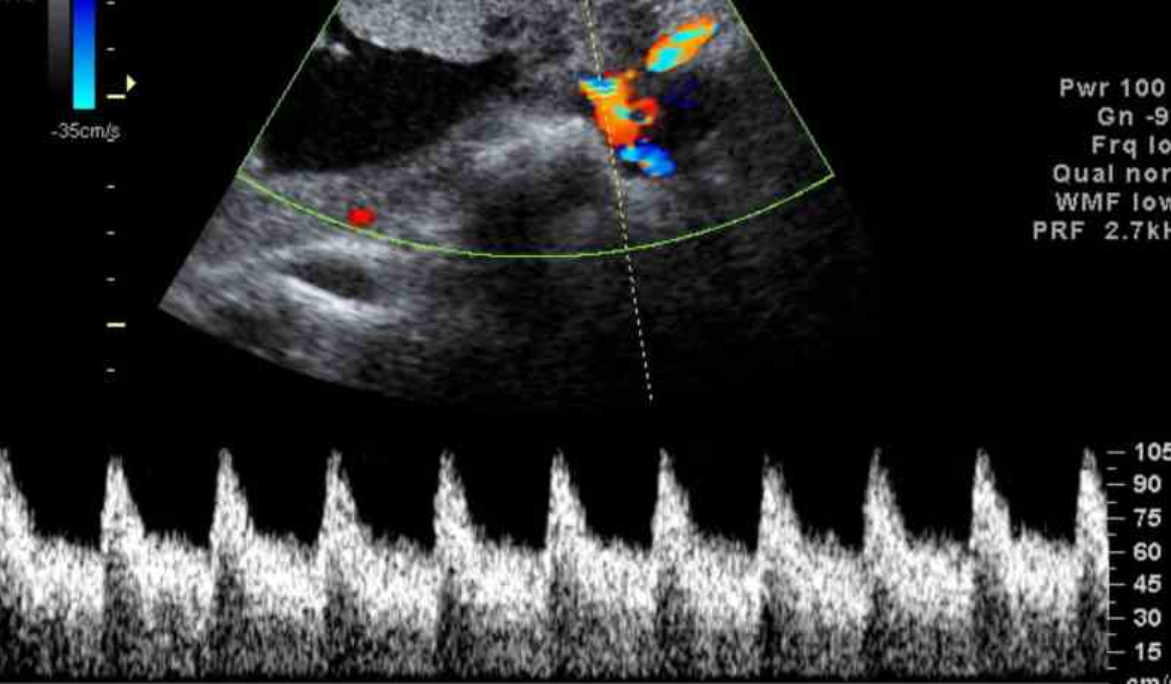

ECOCARDIOGRAFÍA

La ecocardiografía emplea ondas sonoras para producir una imagen del corazón y ver cómo funciona. Según el tipo de estudio ecocardiográfico que se realice, puede determinarse el tamaño, la forma y el movimiento del músculo cardíaco. Este estudio también puede mostrar cómo funcionan las válvulas cardíacas y cómo circula la sangre por el corazón. La ecocardiografía también puede suministrar información sobre las arterias. También se pueden detectar anomalías en la estructura del corazón, tales como defectos en las válvulas cardíacas, anomalías congénitas y aumento del grosor de las paredes o de las cavidades del corazón, como sucede en las personas con hipertensión arterial, insuficiencia cardíaca o deterioro de las paredes musculares del corazón.

La ecocardiografía puede emplearse para detectar un derrame pericárdico, en el cual hay acumulación de líquido entre las dos capas del corazón y la pericarditis constrictiva, en la que se forma tejido cicatricial a lo largo de todo el pericardio. Asì mismo detecta anomalías en el interior de las capas de la pared aórtica. La ecocardiografía es una de las técnicas más ampliamente utilizadas para el diagnóstico de las enfermedades cardíacas puesto que proporciona imágenes de una excelente calidad No invasiva, es inocua y relativamente accesible.